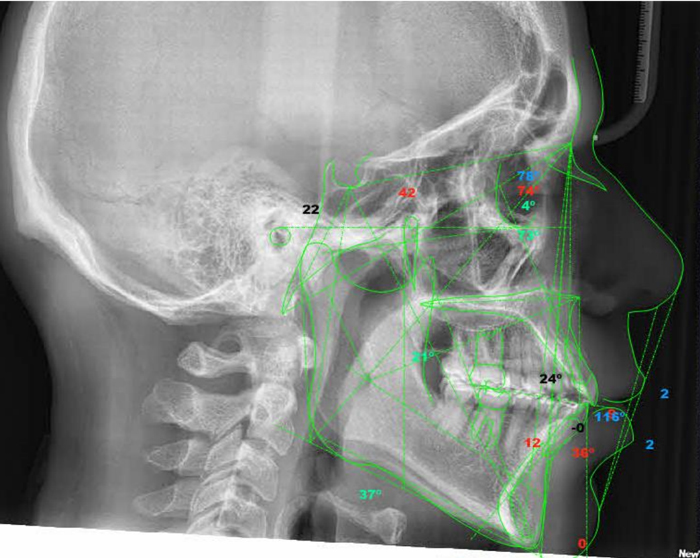

Realizamos estudios de cefalometría digital precisos y detallados, esenciales para el análisis ortodóntico y la planificación de tratamientos correctivos. A partir de una telerradiografía lateral, se aplican métodos de análisis como Jarabak, Roth, Ricketts, Steiner, McNamara y Downs, que permiten evaluar el crecimiento óseo, la simetría facial y la relación entre estructuras dentales y esqueléticas.

Esta cefalometría busca conocer la relación existente entre la altura facial anterior y la posterior del cuerpo maxilar inferior.

En este estudio cefalométrico se analiza la convexidad para interpretar la relación esquelética, entre el maxilar y la mandíbula, y la altura facial inferior, a partir de la cual se representa el patrón muscular del tercio facial inferior.

La cefalometría estática de Ricketts posibilita un minucioso estudio de la morfología craneofacial del paciente, así como las posiciones e interrelaciones de los distintos componentes de las estructuras dentomaxilofaciales.

El análisis cefalométrico de Steiner está basado en la observación de puntos concretos que aparecen en la  telerradiografía lateral de cráneo de donde se obtienen valores con los que se establece la norma para un diagnóstico y un plan de tratamiento adecuados.

La cefalometría de McNamara tiene como objetivo principal realizar un analisis y finalmente un diagnóstico de la morfología y posición de diferentes estructuras del esqueleto facial, estableciendo una relación entre el componente maxilar, el componente mandibular y la base del cráneo.

El trazo cefalométrico de Downs determina la posición y el crecimiento de los maxilares a partir de cinco ángulos para medir prognatismo y retrognatismo mandibular.